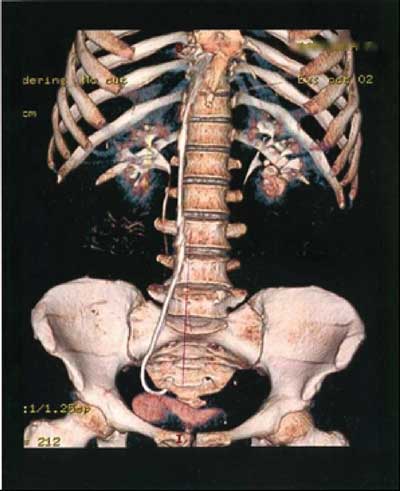

Figure 2

Computed tomography, 3D reconstruction, showing the catheter in the abdominal area.